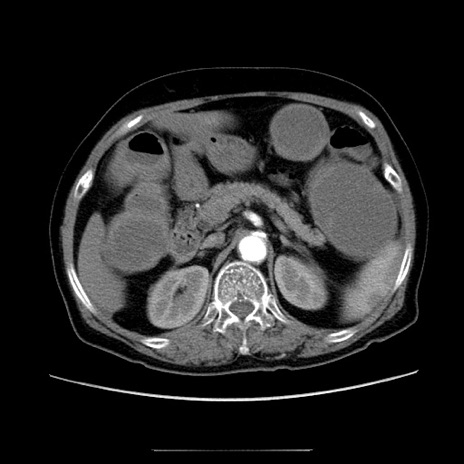

症例5(横断像)

【症例】70歳代女性

【主訴】お腹が張る

【現病歴】1週間くらい前から腹部膨満の自覚あり。昨日夜から増悪したため、本日救急外来受診。

【身体所見】意識清明、BT 36.5℃、BP 165/106mmHg、HR 80bpm、SpO2 98%、腹部:膨満、軟、自発痛・圧痛なし、触診にて不快感あり、腸蠕動音:減弱

【データ】WBC 12600、CRP 1.04